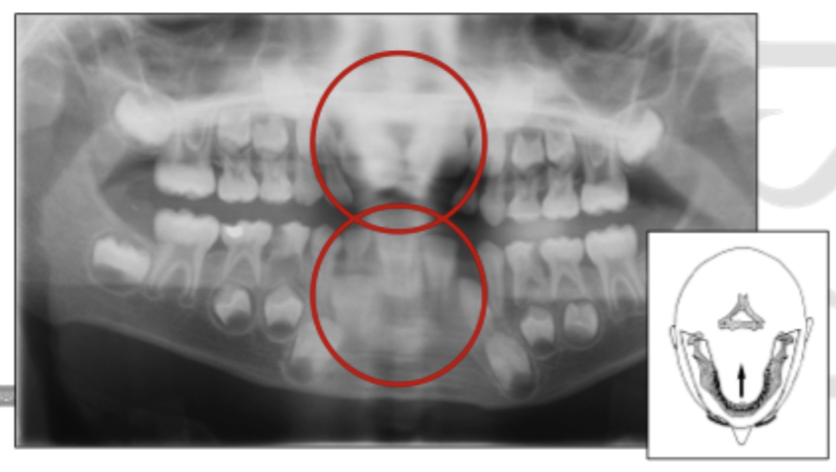

Patient position - Horizontal error

Pt rotated to right → left molar closer to film (smaller) & right molars further from film appear larger.